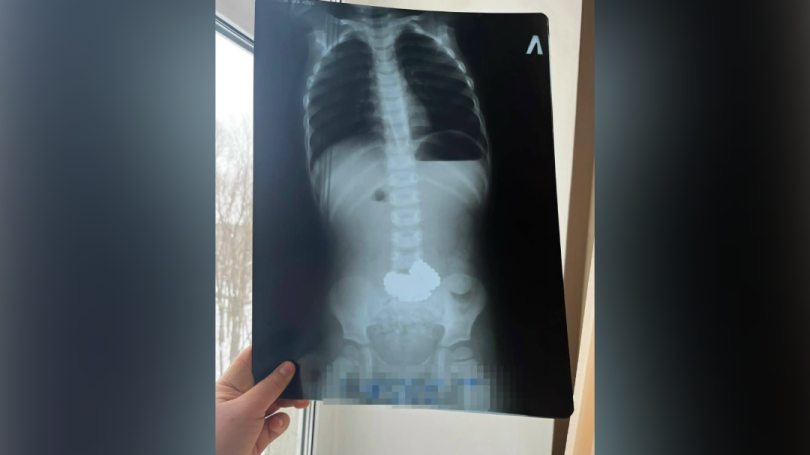

В Башкирии трёхлетний ребёнок проглотил 206 магнитных шариков

Врачам пришлось эстренно спасать малыша. Ребенок увлекался игрой с металлическими шариками и решил провести необычный эксперимент. Родители обнаружили исчезновение игрушек лишь спустя некоторое время, когда ситуация стала критической. Мальчика немедленно доставили в ближайшую медицинскую организацию, откуда экстренно переправили санитарной авиацией в Республиканскую детскую клиническую больницу города Уфа. Здесь хирурги оперативно провели хирургическое вмешательство и осторожно извлекли металлические предметы. Теперь состояние маленького пациента стабилизировалось, угрозы здоровью больше нет. Фото: городская больница Нефтекамска.

Фото: городская больница Нефтекамска.